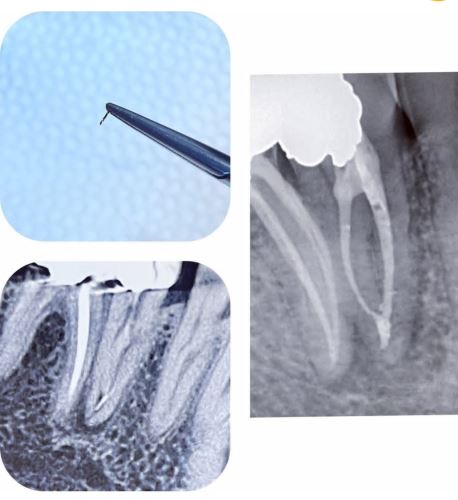

درمان ریشه (Root Canal Therapy)

یک روش دندانپزشکی برای نجات دندانی است که پالپ (عصب و بافت داخلی) آن عفونی یا آسیبدیده شده. این درمان شامل مراحل زیر است:

3. پاکسازی کانالها: خارج کردن پالپ عفونی و تمیز کردن کانالهای ریشه.

4. پر کردن کانال: با مواد مخصوص (مثل گوتا پرکا) برای جلوگیری از عفونت مجدد.

5. ترمیم دندان: معمولاً با روکش برای محافظت و بازگرداندن عملکرد.